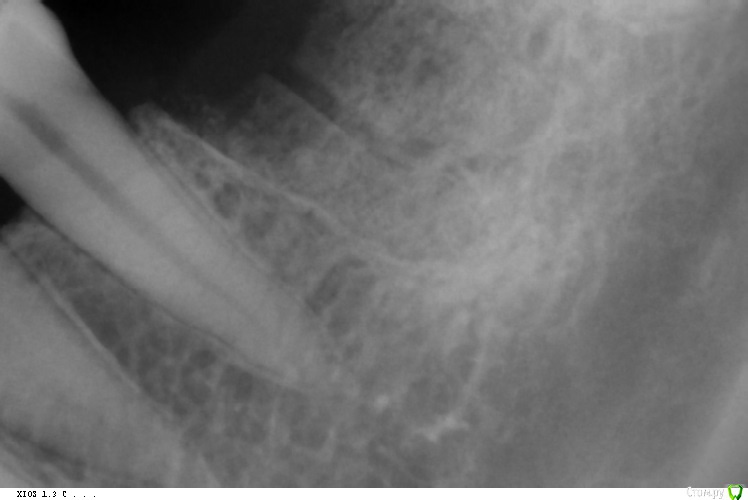

Kast Опубликовано 5 января, 2017 Поделиться Опубликовано 5 января, 2017 (изменено) Здравствуйте, уважаемые доктора! 24.12.16 я в плановом порядке удалила нижний 6-й резорциновый зуб. Прикрепленный панорамный снимок - до удаления. Зуб пришлось выламывать вместе с куском челюсти, затем хирург добавил в лунку 250мг материала био-осс коллаген и закрыл все это мембраной российского производства. Мембраны не хватало, поэтому хирург разрезал ее напополам и сшил так, что шов проходил ровно посередине лунки. 5 дней после удаления все было хорошо, пила антибиотики, мазала лунку солкосерилом, делала ванночки с хлоргексидином, на осмотр 28 декабря я не смогла прийти, но не волновалась, потому что зуб уже совсем не беспокоил. Но еще через два дня лунка начала болеть, и внутри, десна вокруг, 30го и 31го пришлось принимать обезболивание. Клиника и хирург ушли на каникулы, связаться не было возможности. 1го появилась температура 37,5 и держалась 3 дня, 2-го лунка и десна перестали болеть, периодически во рту появлялись кусочки костного материала, момент, когда разошелся шов посреди мембраны, я не отследила. 4-го показалась на приеме у хирурга, он снял швы и убрал сверху мембрану, сказал показаться через месяц. Лунка сейчас вот в таком состоянии, прицельный снимок сделан 2-го января, костный материал продолжает большими кусками отваливаться из лунки, я боюсь, что он весь вывалится и я буду ходить с открытой костью. Врач обещал, что за 100 тысяч удалит зуб и одномоментно поставит имплант, после операции выяснилось, что имплант поставить не получилось, счет только за удаление и биоматериал с мембраной составил 80 тысяч. Мембраны уже нет, биоматериала почти тоже, а теперь по результату за эти деньги у меня только огромная дыра Подскажите, пожалуйста, что-нибудь сейчас можно сделать, чтобы как-то поправить ситуацию? Или остается только ходить с дырой и ждать, пока она сама заживет?Несет ли клиника какую-либо ответственность в таких случаях? Второй день плачу, зачем я полезла удалять этот зуб, который не беспокоил больше 15 лет, только выглядел не эстетично Изменено 5 января, 2017 пользователем Kast Ссылка на комментарий

Kast Опубликовано 5 января, 2017 Автор Поделиться Опубликовано 5 января, 2017 Я бы убрал все из лунки, кюретаж, и провел бы все под 《сгустком крови》, через 3 месяца 3Д снимок и принятие решения о имплантации.К сожалению ситуации разные бывают, по ОПТГ высота кости хорошая, так что думаю все у вас будет хорошоПри удалении не было крови вообще, поэтому врач сделал такую огромную дыру. Сказал, что дальше уже расширять невозможно, там соседние зубы.Добавила фото без "мусора" в лунке, который я приняла за костный материал. Сейчас закладывать в дыру солкосерил или метрогил дента не имеет смысла? Ссылка на комментарий

колесников Опубликовано 6 января, 2017 Поделиться Опубликовано 6 января, 2017 Здравствуйте! Во первых сочувствую Вам. К сожалению это только начало длительной эпопеи заживления. Лунка инфицировала и теперь там альвеолит. Доктора не стоит винить,зуб был не подарок. На снимке видео что верхушки у него имели бутылочное расширение и периодонтальная щель не прослеживалась,все это говорит о технических сложностях при удалении. Доктор должен довести лунку до полного заживления,будьте с ним в контакте,не пропускайте визиты. Рекомендовал бы содовые ванночки дома или слабый марганцевый Р-ор,приём антибиотика ципралет -а или трихопола,аппликации метроном-Дента. Эти рекомендации лучше обсудить с Вашим лечащим врачом. Ссылка на комментарий